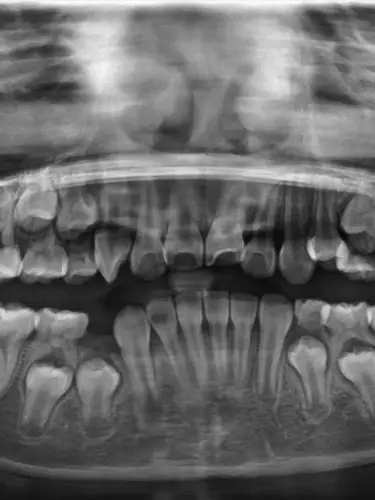

牙齿,x光

儿童牙齿x光片